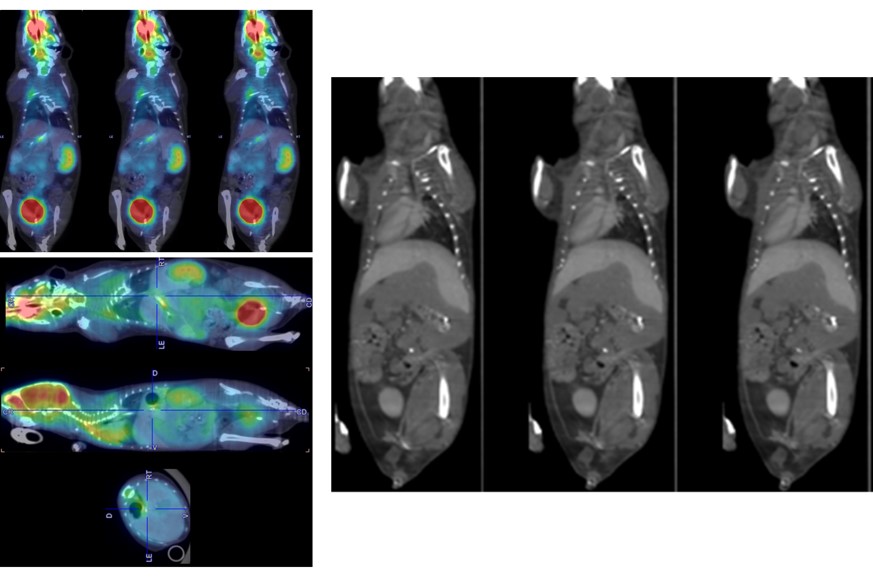

Multi-Animal Dynamic 18FDG-PET/CT in a Mouse Tumor Model

Dynamic PET with low dose injection: 3 MBq 18FDG